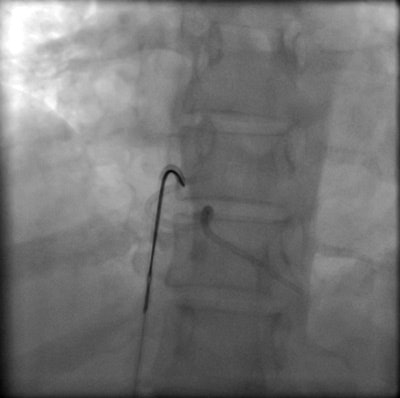

Percutaneous retrieval of the retained fragment of the fractured portacath catheter was successfully accomplished on the second attempt. Following prepping of the right groin, the right femoral vein was punctured and an 8 French sheath was inserted. Selective catheterization of the right ventricle was performed using a 6 French catheter. A 25-mm snare was used to capture the migrated retained fragment. It was then removed successfully without immediate complications.

Percutaneous transcatheter retrieval of the portacath fractured fragment by interventional endovascular techniques is the preferred method of management. GooseNeck loop snare, which we have used in this case, is the most popular device used with a success rate of about 90%.4 If the fractured fragment that has migrated to the heart is not detected and removed early, it becomes endothelialized and may require surgical removal.10